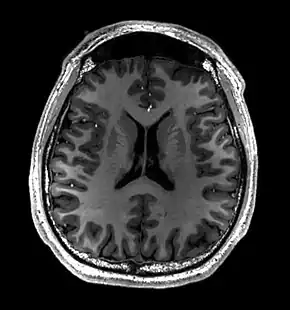

- T1-weighted (T1W) images: Cerebrospinal fluid is dark. T1-weighted images are useful for visualizing normal anatomy.

Brain regions on T1 MRI

T1 (note CSF is dark) with contrast (arrow pointing to meningioma of the falx)